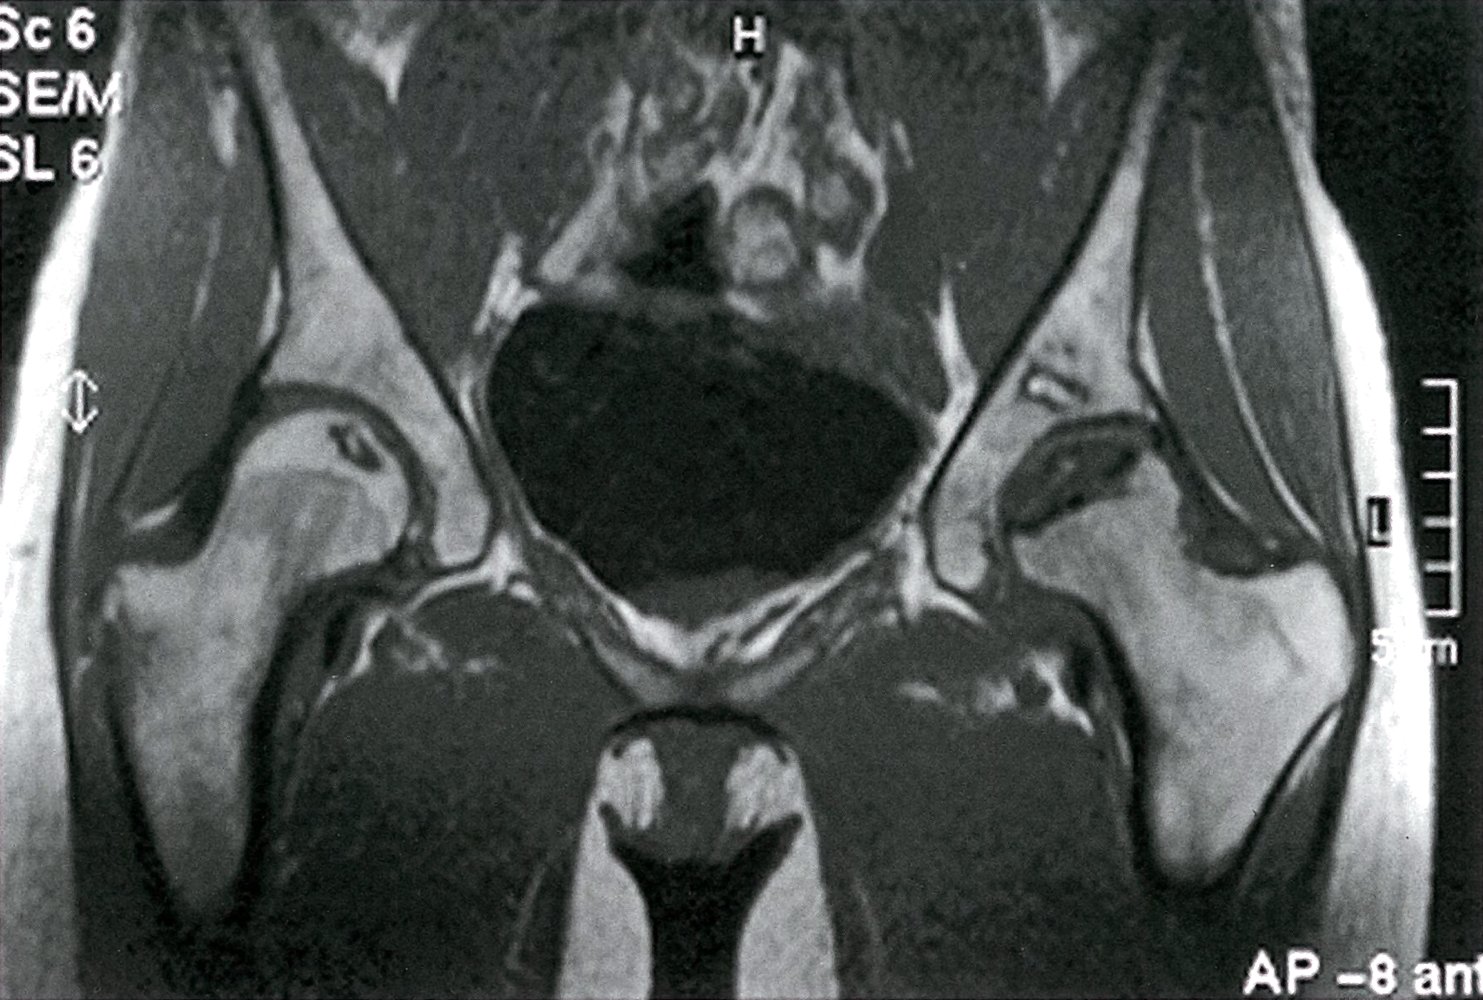

• MRI without contrast [6][8]

• Gold standard(highly sensitive) [2]

• Findings depend on the stage and the bone affected.

Legg-Calvé-Perthes disease

• Femoral head

• Age of onset: 4–10 years

• ♂ > ♀

• Idiopathic disease

• Mismatch between the rapid growth of the femoral epiphyses and the slower development of adequate blood supply to the area

• Antalgic gait (on weight-bearing leg)

• Pain in the hip or the upper leg, sometimes projecting to the knee

• Restricted range of movement

• Contralateral involvement in ∼ 10% of cases